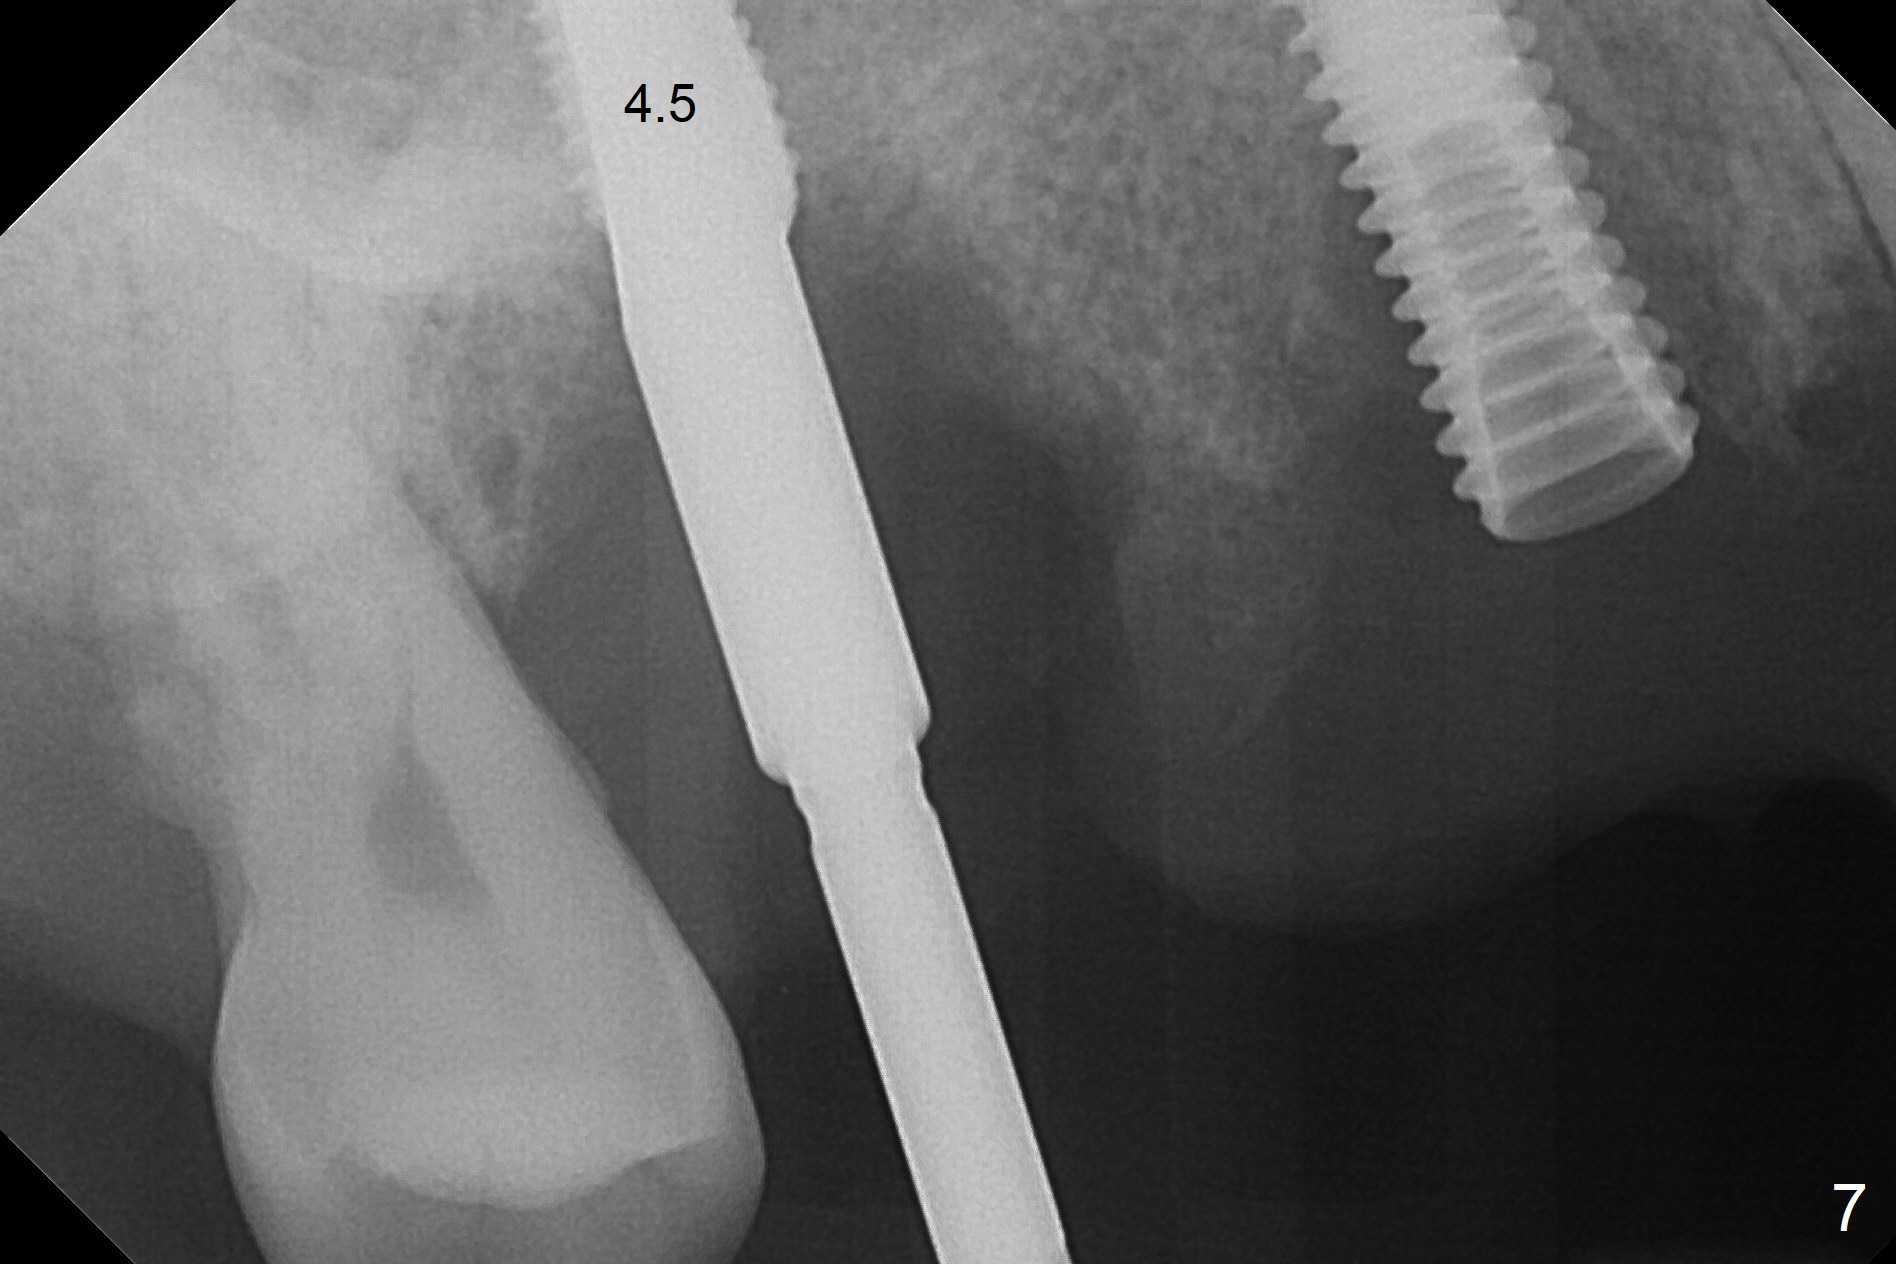

The 36-year-old man (ex-smoker, quit for 4-5 years) insists upon #3 and 5 extraction first for implants, in spite of more severe infection at #7, 14,19,30 (Fig.1-4). The gingiva around #23-26 implants is healthy 3 weeks postop (Fig.5). The initial depths at #3 and 5 are 8.5 mm (bone-level) and 18 mmm (gingiva-level (13 mm (implant length) + 5 mm cuff), respectively. When a drill penetrates the sinus floor, confirm the depth. After use of 3.8 mm drill, 4.5 mm tap drill is inserted at #3 without stability, while a 4.5x13 mm implant is placed at #5 with primary stability (Fig.6,7). Then a 5x11.5 mm is placed at #3 subcrestal proximally after sinus lift with Vanilla graft (without sinus membrane perforation; Fig.8). The implant at #5 is seated ~1 mm deeper (subcrestal mesially (^^); supracrestal distally (^)); allograft is placed around the implants prior to insertion of 6.5x7(5) and 5.5x4(5) mm abutments; last more allograft is added (Fig.9 *, 10). The implants seem to have been osteointegrated 4.5 months postop (Fig.11,12). The gingiva is healthy around the implants without bone loss 3 months post cementation (Fig.13,14).